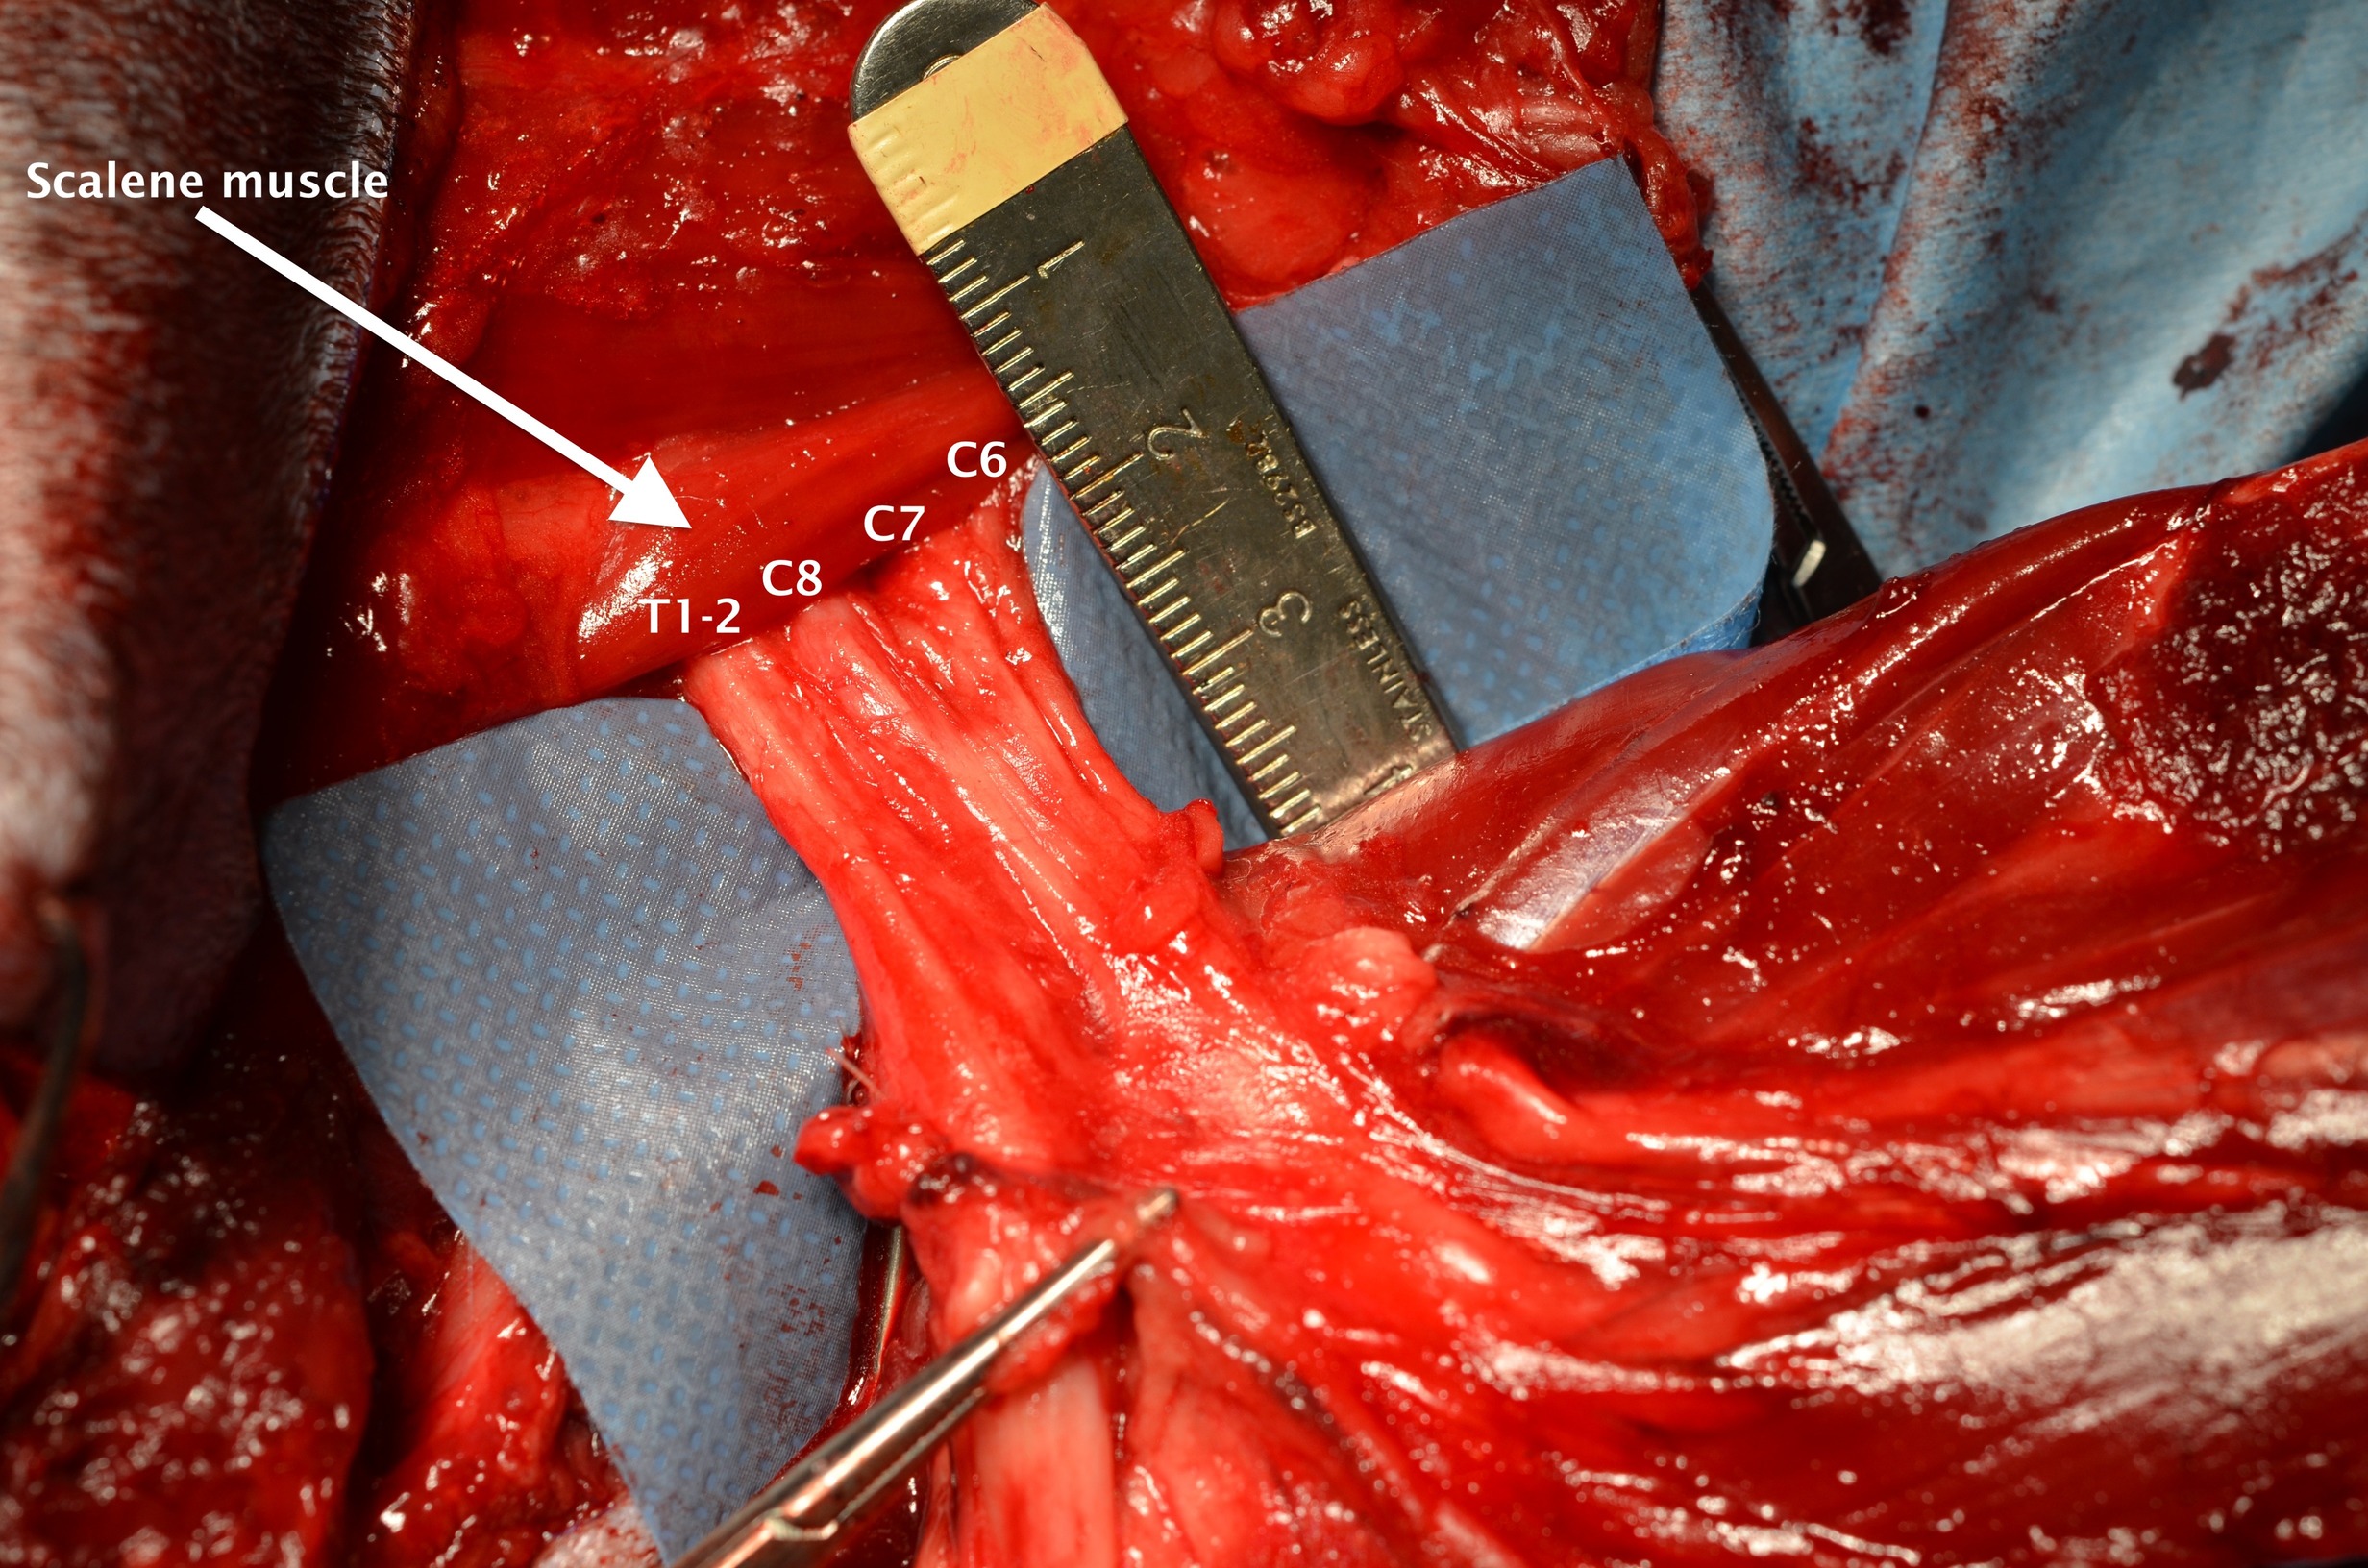

Following specialist interpretation, the CT report was highly suggestive that Poppy had a tumour within her brachial plexus (Nerve roots of the leg) and radial nerve in her right forelimb. Poppy’s owners consented to surgery. During surgery the affected forelimb was amputated including her shoulder blade to allow Martin to remove her brachial plexus

During the surgery, Martin ligated the large blood vessels and used diathermy to cauterize the smaller vessels within the muscles and soft tissue to reduce the risk of bleeding. The swelling and hard tissue that was noted in the CT report was identified, and the brachial plexus was removed.